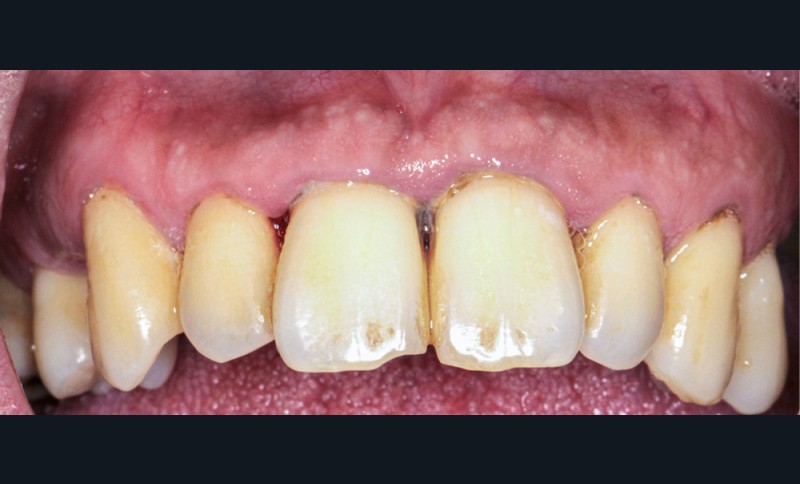

L’obésité, définie par un indice de masse corporelle (IMC) ≥ 30 kg/m2, est une maladie inflammatoire chronique complexe et multifactorielle caractérisée par un dépôt excessif de graisse dans le tissu adipeux. Selon l’OMS, depuis 1975, le nombre de cas d’obésité a presque triplé à l’échelle planétaire [1]. En 2020, près d’un Français sur deux était en surpoids, tandis que 17 % étaient obèses [2]. Or l’obésité est responsable d’une haute mortalité à l’échelle mondiale et est un facteur de risque majeur pour de nombreuses maladies, dont les maladies cardiovasculaires, le diabète de type 2 et certains cancers [1]. Son impact sur la santé des populations et son coût économique et social sont donc considérables. Ces deux dernières décennies, de nombreuses études ont montré que l’obésité pouvait aussi être incriminée dans la détérioration de la santé bucco-dentaire [3] (fig. 1 à 7).